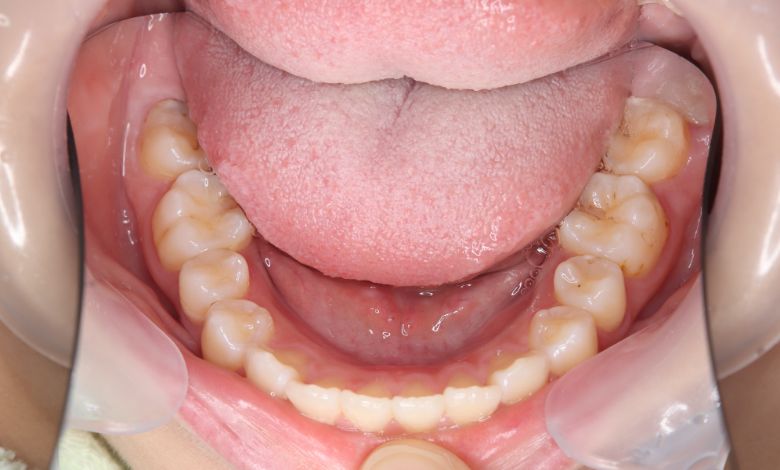

下の前歯が3本、強く重なり合って生えており、歯並びの乱れが目立つ

下顎の歯列では、前歯部に強い重なりが見られ、中切歯および側切歯がねじれたり前後にずれて生えているのが確認できる

術前に認められた前歯3本の強い重なりは完全に解消され、スムーズな歯列が形成されました。

精密検査の結果、抜歯を行わずに歯列弓を拡大する治療方針を選択。歯が正しい位置に並ぶスペースを

確保したことで、歯列は自然なU字型に整い、叢生が解消されました。見た目の改善だけでなく、

咀嚼機能の向上や清掃性の改善といった機能面での効果も期待できます。